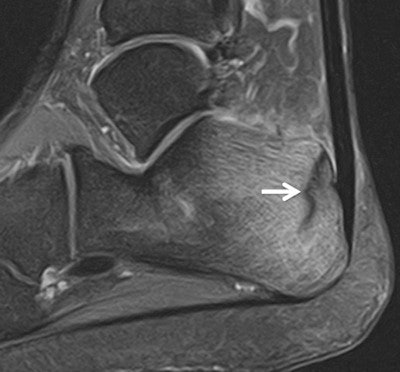

However, in the run to the games they have seen several typical sports injuries, including a fatigue stress fracture in the heel of a long distance runner and a case of iliotibial band syndrome in the knee of a hockey player (see images).